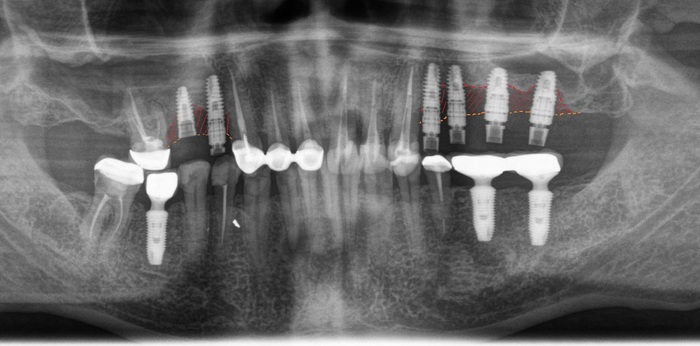

Ниже, на панорамном снимке зубов, мы наблюдаем критичную убыль костной ткани вокруг имплантатов на верхней челюсти.

Оранжевая пунктирная линия - было,

красная - стало.